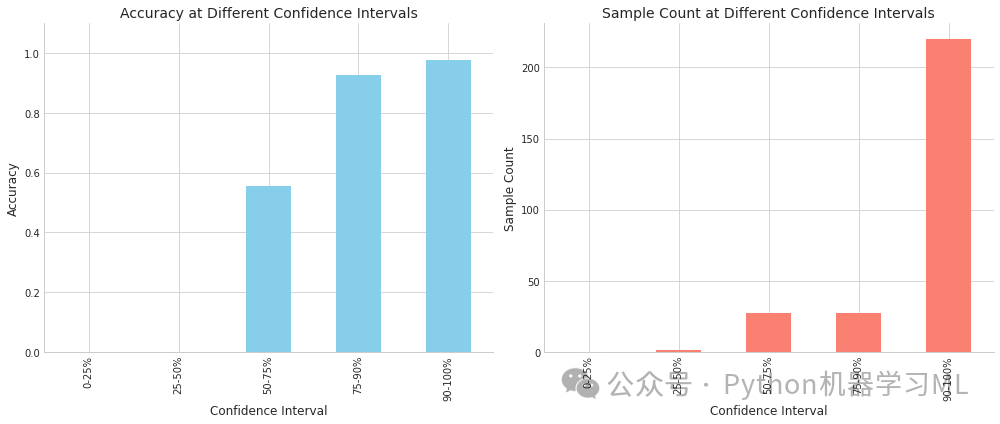

第三阶段:模型样本难度分析

这部分代码分析模型对不同样本的分类难度,通过预测置信度与准确率的关系,识别难分样本和易误判样本。

python# 模型样本难度分析

defanalyze_sample_difficulty(y_true, y_pred_proba, categories):

"""

分析模型对样本的分类难度

参数:

y_true: 真实标签

y_pred_proba: 预测概率

categories: 类别名称列表

返回:

按置信度排序的结果数据框

"""

# 计算每个样本的预测置信度

confidences = np.max(y_pred_proba, axis=1) # 获取每个样本的最大预测概率作为置信度

predicted_classes = np.argmax(y_pred_proba, axis=1) # 获取预测类别

correct_predictions = (predicted_classes == y_true) # 判断预测是否正确

# 创建结果数据框

import pandas as pd # 导入pandas用于数据处理

df = pd.DataFrame({

'True_Class': [categories[y] for y in y_true], # 将真实类别索引转换为类别名称

'Predicted_Class': [categories[y] for y in predicted_classes], # 将预测类别索引转换为类别名称

'Confidence': confidences, # 预测置信度

'Correct': correct_predictions # 预测是否正确

})

# 按置信度排序

df_sorted = df.sort_values('Confidence') # 按置信度升序排序

# 分析不同置信度区间的准确率

confidence_bins = [0, 0.25, 0.5, 0.75, 0.9, 1.0] # 定义置信度区间边界

bin_labels = ['0-25%', '25-50%', '50-75%', '75-90%', '90-100%'] # 区间标签

df['Confidence_Bin'] = pd.cut(df['Confidence'], confidence_bins, labels=bin_labels) # 将置信度分箱

bin_accuracy = df.groupby('Confidence_Bin')['Correct'].mean() # 计算每个区间的准确率

bin_counts = df.groupby('Confidence_Bin')['Correct'].count() # 计算每个区间的样本数量

# 绘制置信度与准确率的关系

plt.figure(figsize=(14, 6)) # 创建14x6大小的图形

# 准确率条形图

plt.subplot(1, 2, 1) # 创建1x2网格的第1个子图

bin_accuracy.plot(kind='bar', color='skyblue') # 绘制条形图

plt.title('Accuracy at Different Confidence Intervals') # 设置标题

plt.xlabel('Confidence Interval') # 设置x轴标签

plt.ylabel('Accuracy') # 设置y轴标签

plt.ylim(0, 1.1) # 设置y轴范围

# 样本数量条形图

plt.subplot(1, 2, 2) # 创建1x2网格的第2个子图

bin_counts.plot(kind='bar', color='salmon') # 绘制条形图

plt.title('Sample Count at Different Confidence Intervals') # 设置标题

plt.xlabel('Confidence Interval') # 设置x轴标签

plt.ylabel('Sample Count') # 设置y轴标签

plt.tight_layout() # 调整布局

plt.show() # 显示图形

# 返回难以分类的样本(低置信度但预测正确,或高置信度但预测错误)

hard_correct = df[(df['Confidence'] < 0.6) & df['Correct']].sort_values('Confidence') # 低置信度但预测正确的样本

hard_incorrect = df[(df['Confidence'] > 0.8) & ~df['Correct']].sort_values('Confidence', ascending=False) # 高置信度但预测错误的样本

print("\n=== Difficult but Correct Samples (Low Confidence) ===") # 打印标题

iflen(hard_correct) > 0: # 如果存在此类样本

print(hard_correct.head(5)) # 打印前5个样本

else: # 如果不存在此类样本

print("No such samples") # 打印无样本信息

print("\n=== Incorrectly Classified with High Confidence (Model Confidently Wrong) ===") # 打印标题

iflen(hard_incorrect) > 0: # 如果存在此类样本

print(hard_incorrect.head(5)) # 打印前5个样本

else: # 如果不存在此类样本

print("No such samples") # 打印无样本信息

return df_sorted # 返回按置信度排序的数据框

# 分析样本难度

difficulty_analysis = analyze_sample_difficulty(y_valid, y_pred, categories) # 调用样本难度分析函数

=== Difficult but Correct Samples (Low Confidence) === True_Class Predicted_Class Confidence Correct Confidence_Bin241 Bengin cases Bengin cases 0.509895 True 50-75%210 Normal cases Normal cases 0.512126 True 50-75%252 Normal cases Normal cases 0.527766 True 50-75%48 Malignant cases Malignant cases 0.554800 True 50-75%256 Bengin cases Bengin cases 0.565877 True 50-75%

=== Incorrectly Classified with High Confidence (Model Confidently Wrong) === True_Class Predicted_Class Confidence Correct Confidence_Bin160 Bengin cases Normal cases 0.994491 False 90-100%151 Bengin cases Normal cases 0.990153 False 90-100%238 Bengin cases Normal cases 0.989127 False 90-100%113 Malignant cases Normal cases 0.957777 False 90-100%181 Bengin cases Normal cases 0.953322 False 90-100%

样本难度分析:

-

- 基于预测置信度分析模型对不同样本的分类难度

- 研究置信度与准确率的关系,验证模型校准性

- 识别特别难以分类的样本(低置信但正确)和易误判样本(高置信但错误)